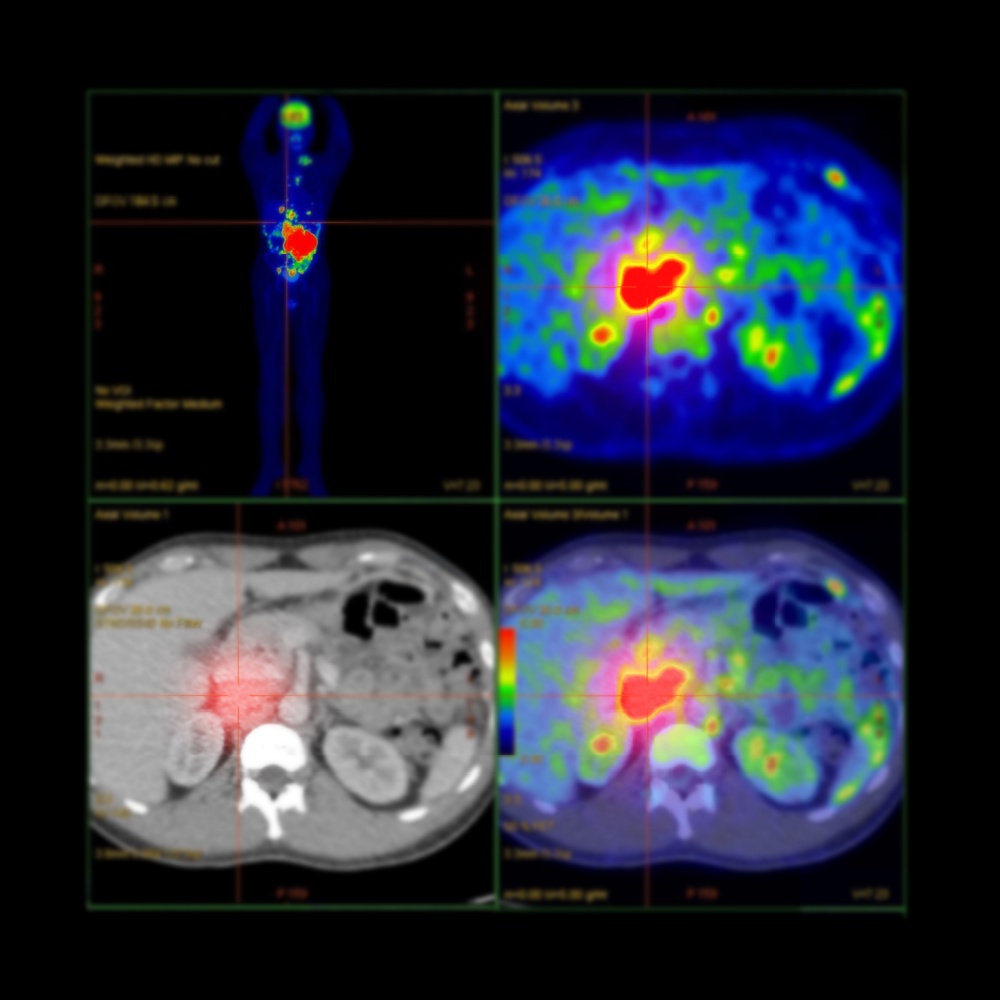

E o que significam as cores?

Um dos pontos que mais chamam atenção no exame são as imagens coloridas. Essas cores representam o nível de atividade metabólica em diferentes regiões do corpo. De forma geral:

Preto ou azul: baixa atividade metabólica ou nenhuma captação significativa do marcador.

Verde ou amarelo: atividade metabólica moderada, observada em tecidos normais ou inflamação leve.

Vermelho ou branco: alta atividade metabólica, indicando alta captação de glicose, como em tumores ou inflamações.

A intensidade da cor nas imagens de PET indica o nível de atividade metabólica. Cores de maior intensidade significam maior atividade metabólica. Cores de menor intensidade indicam menor atividade.

No entanto, atenção! Isso não significa necessariamente presença de câncer. Processos inflamatórios, infecções e até o funcionamento normal de alguns órgãos podem gerar imagens semelhantes.